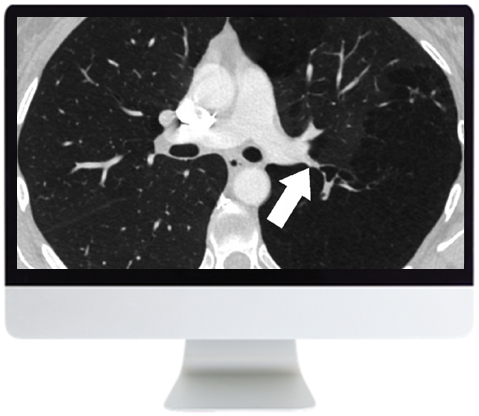

- Management of Solid Pulmonary Nodules: Characterization and Update — J. Ko

- Adenocarcinoma and the Subsolid Nodule: Current Concepts — J. Ko

- Nodular Pattern on Chest CT — D. Manos